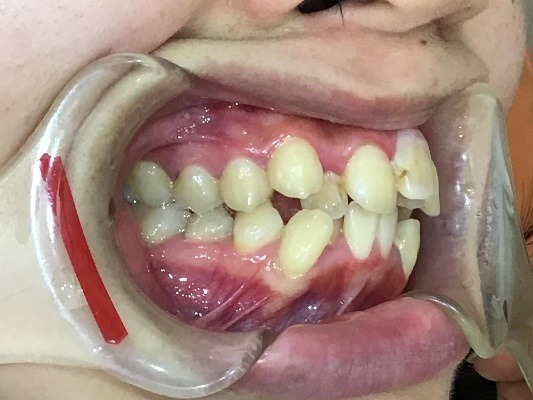

正面

右横

| 治療詳細 | 叢生や交叉咬合を整えるために、歯の表面にアタッチメント(白い突起)をつけ、IPR(歯と歯の間を削る)を行いました。 また、顎間ゴムと呼ばれる引っ掛けるゴムの補助装置も用いて治療を行いました。 抜歯を1本して治療を行いました。該当部分は義歯を使用しています。 |

| 主訴 | 歯のがたつき 一部分だけかみ合わせが反対 |